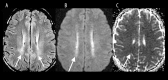

Toxic leukoencephalopathy results from damage to the white matter caused by various toxins. It manifests itself as white matter signal abnormalities with or without the presence of restricted diffusion. These changes are often reversible if the insulting agent is removed early, with the exception of posthypoxic leukoencephalopathy that can manifest itself 1-2 weeks after the initial insult. However, many other potential causes of white matter signal abnormalities can mimic the changes of toxic leukoencephalopathy. Thus, familiarity with the causes, clinical presentation and particularly imaging findings of toxic leukoencephalopathy is critical for early treatment and improved prognosis. The purpose of this pictorial essay is to familiarize the reader with the various causes of toxic leukoencephalopathy along with its differential diagnoses and mimics.